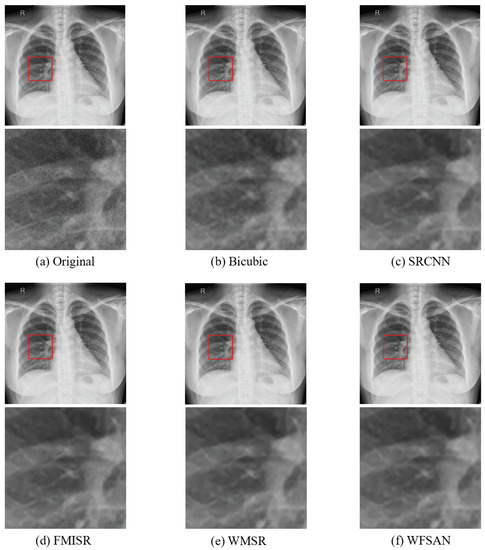

4.2. Quantitative Results

4.4. Discussion